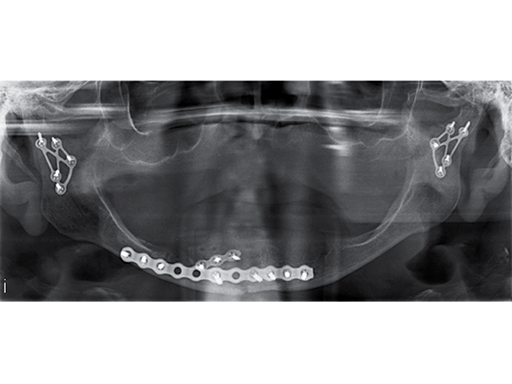

Fig 3: Postoperative panoramic x-ray